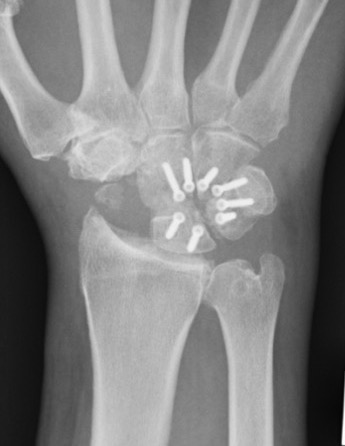

Scaphoidectomy & Limited arthrodesis

Indication

Stage II / III: Preserved radio-lunate joint

Concept scaphoidectomy + limited arthrodesis

| 4 corner fusion | 4 corner / bicolumn | 3 corner fusion | 2 corner fusion |

|---|---|---|---|

|

Capitate - lunate Triquetrum-hamate-capitate

Capitate-lunate Triquetrum-hamate |

Capitate - lunate Capitate - hamate +/- triquetrum excision |

Capitate - lunate |

Fixation options

K wires

Headless compression screws

Dorsal locking plates

4 corner fusion techniques

4 corner: capitate / lunate screw + triquetrum / hamate / capitate screw

Bi-column: capitate / lunate screw + triquetrum / hamate screw

Vumedi scaphoidectomy and four corner fusion with screws

Arthrex scaphoidectomy and four corner fusion with staples

Acumed four corner fusion plate surgical technique PDF